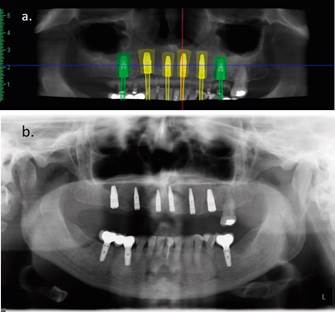

Posteriormente, este enfilado se transforma en guía radiográfica, agregando marcadores radiopacos en dientes específicos (Figura 2c). Los marcadores radiográficos se confeccionan con bandas de láminas de plomo de 2 mm de ancho y adheridas de vestibular a palatino hasta el límite amelo-cementario. Se solicita un Cone Beam Computarized Tomography (CBCT) con la guía radiográfica y, con el software del CBCT (Romexis®, Planmeca), se realiza el análisis de los sitios y la planificación digital 3D. Se seleccionan implantes Roxolid SLA® Bone Level Tapered (Straumann®), respetando distancias biológicas de Tarnow et al9 y Grunder et al10. Se planifican implantes de 4.8x12mm. para sitios 1.6 y 2.6; de 3.3x14mm. para 1.1 y 1.3; y de 3.3x12mm. para 2.1 y 2.3.

La guía radiográfica usada anteriormente es transformada en guía quirúrgica no estricta, perforando los sitios donde se instalarán los implantes para el paso de la fresa piloto. La cirugía se efectúa bajo anestesia local con técnica infiltrativa maxilar. Se realiza incisión supracrestal y colgajo semi Newman bilateral con descarga vertical hacia distal. Luego, se realizan osteotomías y la instalación de los implantes quedando todos sumergidos, con un torque de inserción mayor a 40Ncm. Se toma radiografía panorámica de control inmediato post-cirugía (Figura 4). La PR de la paciente se espacía para no sobrecomprimir tejidos blandos. Se controla a los 7 días, donde se retiran las suturas y se rebasa prótesis con rebasador blando (COE Soft, GC®). Posteriormente, se realizan controles mensuales sin complicaciones.